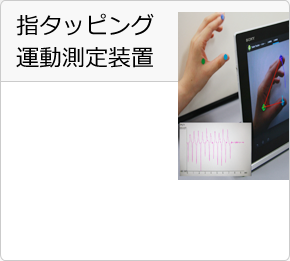

Andoroidタブレットで使用可能な簡易解析アプリケーションをご紹介。医療現場での使用や探索先での解析に威力を発揮します。